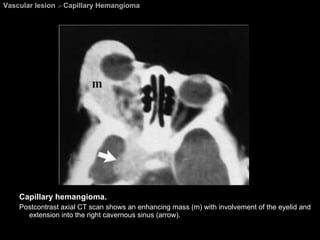

Vascular lesion  >  Capillary Hemangioma Capillary hemangioma.  Postcontrast axial CT scan shows an enhancing mass (m) with involvement of the eyelid and extension into the right cavernous sinus (arrow).